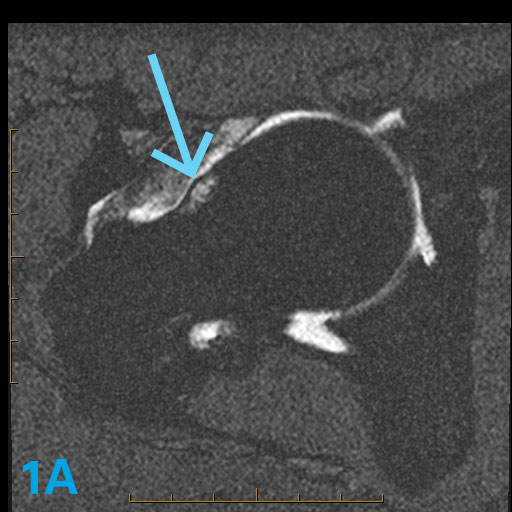

The three axial oblique images in this 43-year-old with hip pain demonstrate an abnormality. What are the associated potential imaging findings that might accompany this abnormality?

The lack of tapering of the femur head to the neck is known as asphericity. This lack of tapering is associated with a bump in the anterior aspect of the femoral head neck junction. The bump is also associated with a friction-related pseudocyst ("herniation pit") that occurs when the hip is in flexion and especially in flexion-internal rotation as this area rubs across the acetabulum. Sometimes the friction produces edema but not an actual cyst.

- In such a patient, the alpha angle (if measured) would be elevated.

- An abrasion, ulcer or erosion would often be seen in the far anterior superior acetabulum as this bump rides against and abrades or erodes the cartilage of the acetabular roof.

- Labral tears and detachments are frequent.

Clinically, such patients often experience pain in hip flexion worse in internal more than external rotation. This case illustrates an axial oblique head neck junction shape of Cam or Type 1 hip impingement syndrome. For more case review, check out MRI Online.